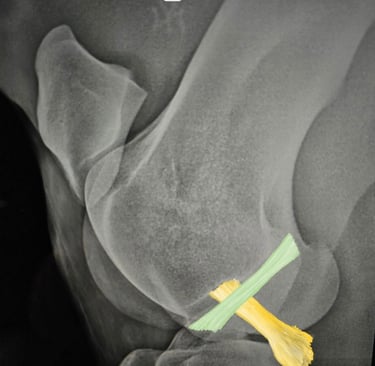

Región femoro tibio rotuliana, anatomia, biomecanica y casos -

CURSO COMPLETO